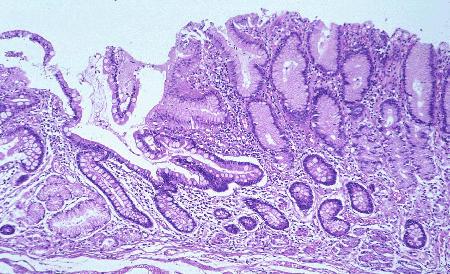

メッケル(Meckel)憩室の病理組織像(ミクロ)  (id:1068)の一部を拡大したものです。左は腸の粘膜で、右は異所性の胃粘膜がみられます。中央部には、浅いびらんが認められます。

疾患(病理主体)の分類憩室/メッケル(Meckel)憩室

部位(臓器別)小腸/その他

検査方法ミクロ